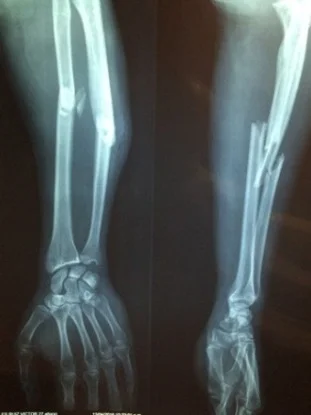

Orthopaedics

This specialization is related to diseases and wounds of the hard-pincer or musculoskeletal system of your body. MBBS students who have studied Orthopedics can do MD in this subject.